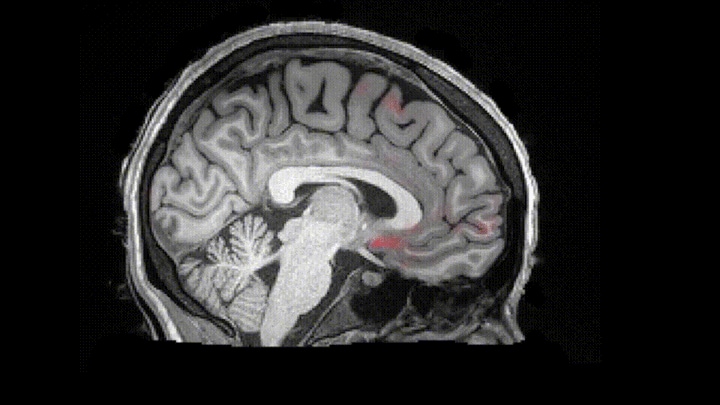

米ボストン大学の研究チームは、高速撮像技術を用いて、ノンレム睡眠中における脳脊髄液の律動を初めてとらえ、脳脊髄液の動きと脳波の活動、血流が密接に結びついていることを示した。この研究成果は、2019年10月31日、学術雑誌「サイエンス」で公開されている。

そこで研究チームは、23歳から33歳までの成人13名を対象に、脳波(EEG)ヘッドセットで脳波を測定するとともに、MRI(磁気共鳴断層撮影装置)を用いてノン睡眠時の脳脊髄液の様子をモニタリングし、脳波において周波数の低い波が多くなると、脳の血流が低下し、脳脊髄液が脳内に流れ込むことを示した。ニューロン(神経細胞)が遮断されると、それほど酸素を必要としないため血液が減り、血液が流出すると脳内の圧力が低下するので、脳圧を安全なレベルに保つべく脳脊髄液が急速に流れ込むものと考えられる。